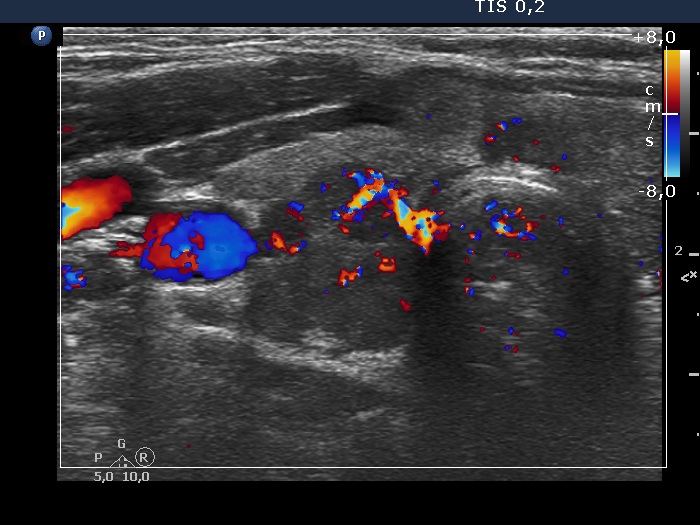

Right lobe, longitudinal scan

Right lobe, transverse view, color Doppler mode. The vascularization is average.